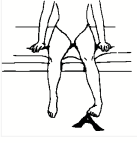

Έκταση του γόνατος ενώ είστε καθιστοί (με κίνηση)

Καθίστε ευθυτενείς σε μια καρέκλα και ακουμπήστε τα πόδια σας στο πάτωμα. Σιγά-σιγά σηκώστε και ισιώστε το πόδι που σας πονά μέχρι να νιώσετε τους μηρούς σας να σφίγγουν. Κρατήστε το πόδι σας σε αυτή τη θέση και ύστερα επιστρέψετε στην αρχική θέση. Επαναλάβετε την άσκηση 10 φορές.